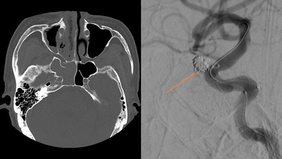

Complex Vertebro-Basilar Junction Aneursym

By Siddhant SINGH

Published on December 11, 2025